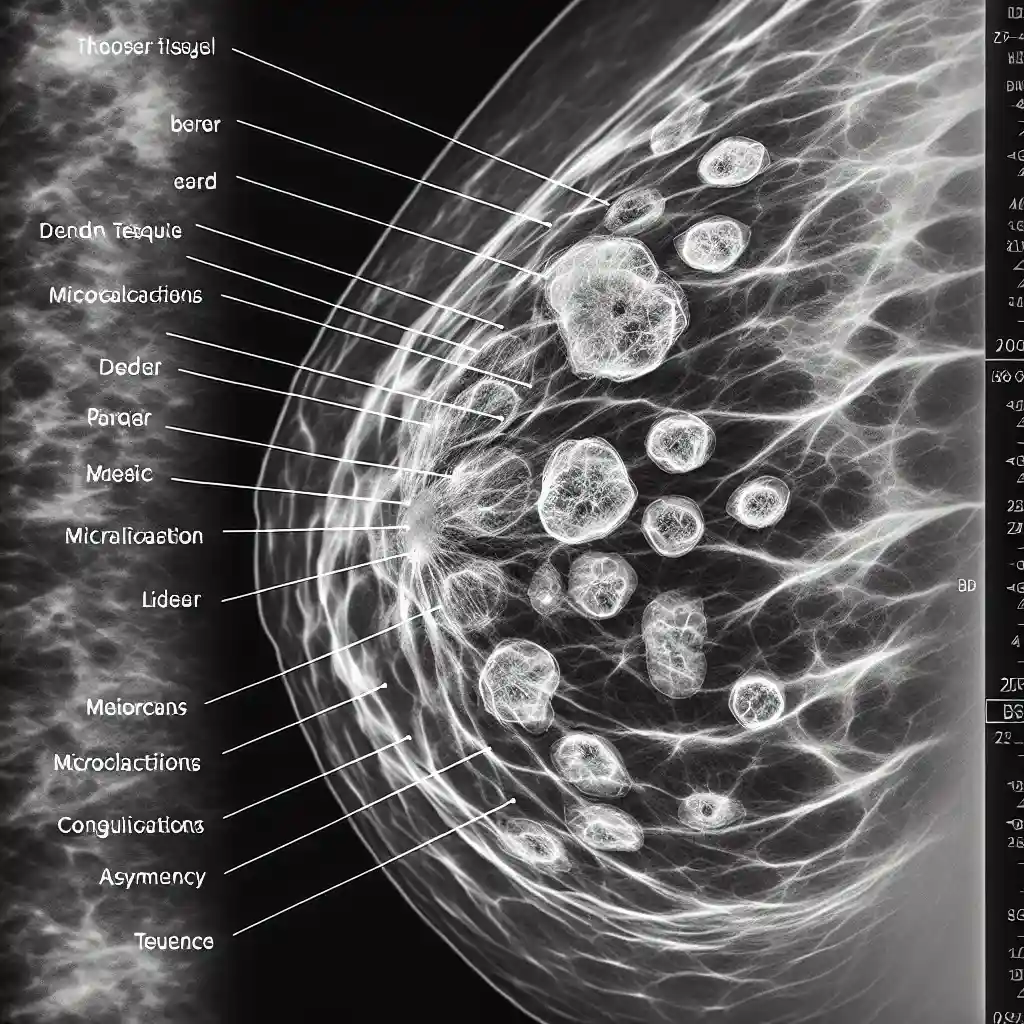

Как выглядит рак на маммографии

Маммография – ключевой метод раннего выявления рака молочной железы, позволяющий диагностировать заболевания ещё на начальных стадиях. Как выглядит рак на маммографии и какие признаки указывают на патологию? В этом материале мы подробно рассмотрим визуальные особенности опухоли, основные симптомы на снимках и рекомендации специалистов, чтобы помочь женщинам и врачам своевременно распознавать опасные изменения. Знание этих особенностей повышает шансы на успешное лечение и сохранение здоровья.

Если вы хотите глубже разобраться в деталях маммографии и понять, как отличить злокачественные образования от доброкачественных, читайте далее. Наши советы и примеры снимков помогут вам ознакомиться с важнейшими аспектами диагностики рака груди.